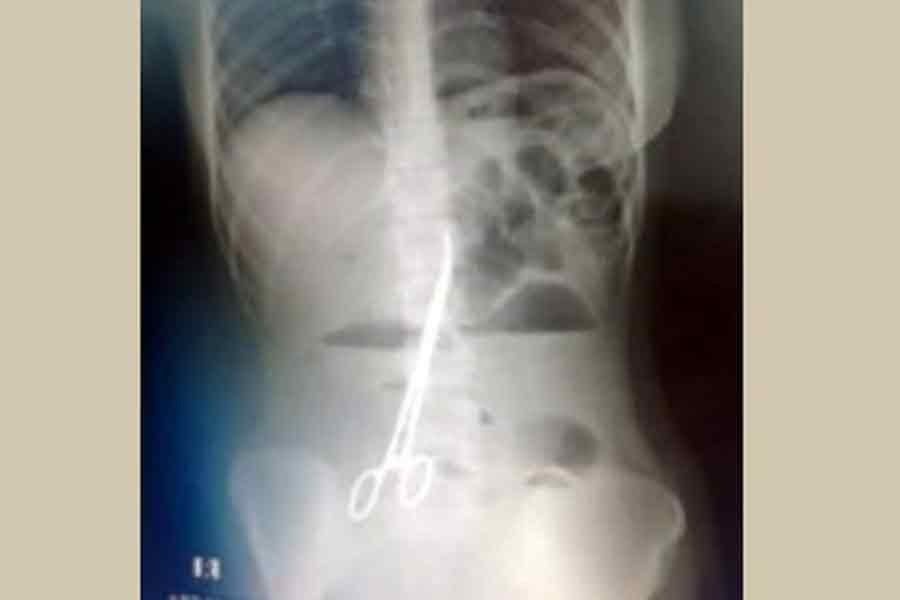

A doctors' group probing an incident at the Bangabandhu Sheikh Mujib Medical College Hospital in Faridpur, during which a pair of six-inch surgical scissors were left in a girl’s abdomen after surgery and stayed there for 21 months, has found that no one was specifically responsible for the error.

Surgery was performed on 18-year-old Monira Khatun on Mar 3 last year after she sought treatment from the hospital for a blood-clot problem in her abdomen.

She recently visited the hospital again due to regular pain. An X-ray of her abdomen showed that surgeons had left a pair of scissors in her body during the surgery.

She had another operation at the same hospital on Dec 11 to remove the scissors. The probe committee was formed to investigate the incident on Sunday.